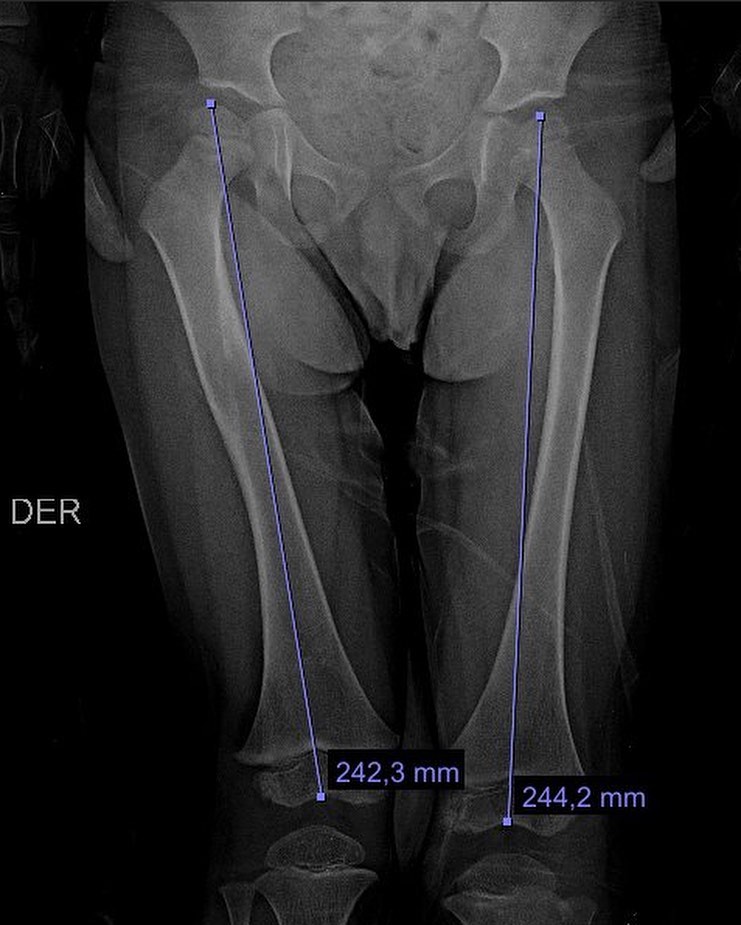

Fractura de fémur

El año pasado mi pacientito Dylan se fracturó el fémur, realizamos tratamiento conservador y ahora está al 💯 Vino a consulta y recibí este delicioso regalo, ¡muchas gracias Dylan!

El año pasado mi pacientito Dylan se fracturó el fémur, realizamos tratamiento conservador y ahora está al 💯 Vino a consulta y recibí este delicioso regalo, ¡muchas gracias Dylan!